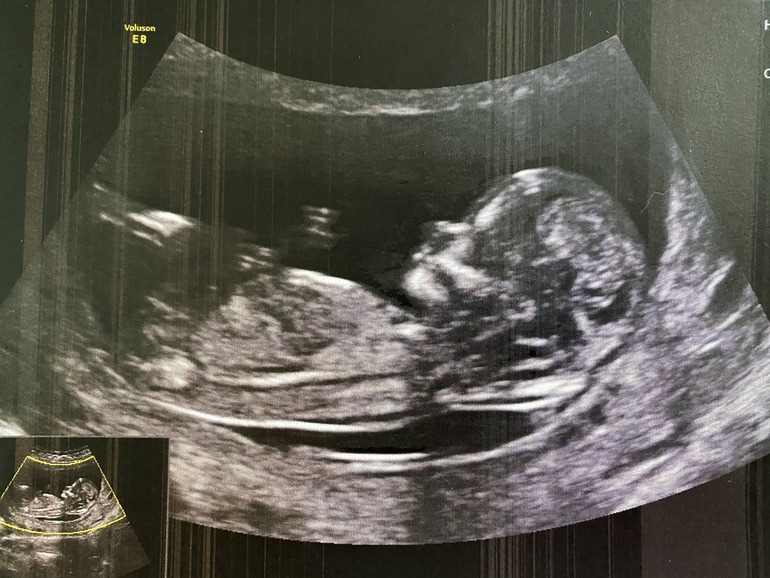

Пол малышаСрок 12,6 по узи.

Конечно хочется узнать кто там в домике живет. Узистка предположила на 80% (не напишу какой, чтобы не было предвзятости 😅).

Как думаете кто это - мальчик или девочка?

Если это оно, куда смотрю, то девочка, видимо. Хотя снимок так себе, ну, именно того места😊 Так-то, замечательный ребёнок в профиль.